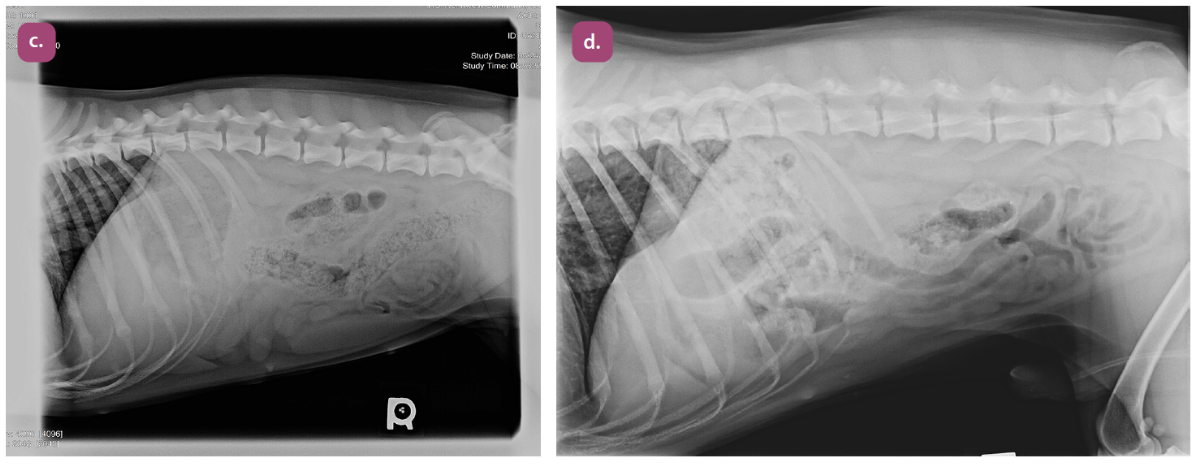

lateral projection of the thorax

ventrodorsal projection of the thorax

ventrodorsal projection of thorax with the horizontal beam (lateral decubitus)